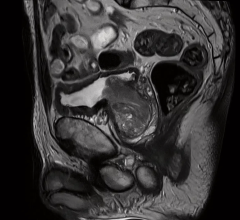

From the exhibit floor, Siemens launched a version of the go.Top CT scanner dedicated for cardiology, its compact footprint and pricing (south of $800,000) designed to fit the physical spaces of outpatient centers and their budgets. The underlying Go platform suits patients as well with a gantry-hung PC tablet that can take the place of a control room and, thereby, allows the technologist to spend more time directly with patients. (A radiological version of the 128-slice Siemens go.Top was released at the Radiological Society of North America’s (RSNA) 2017 conference.) In line with its patient centricity is the CARE kV feature, which optimizes radiation dose and image contrast, and its Check&GO algorithm, which helps identify problems with anatomical coverage and the distribution of media contrast.

Although optimized for outpatient cardiology offices, the CV version of the CT might also be installed in hospitals, according to Matthew Dedman, Siemens’ director of CT product marketing. Siemens has developed a technical solution that optimizes data transmission from the scanner to the company HeartFlow, where CT-based fractional flow reserve (FFR) analyses may be conducted. This solution can then be leveraged for the transmission of results back to the physician.

Similarly, GE Healthcare directed booth goers to its Cardiographe, a CT scanner launched some two years earlier. Philippe Karam, GE’s global sales and marketing director, noted the CardioGraphe’s dedication to cardiology and cost-effectiveness, stating that the system had been built specifically for the cardiology market. It can be used to plan procedures including transcatheter aortic valve replacement (TAVR), according to Kira Behrens, GE’s director of premium CT for the U.S. and Canada. Dose efficiency is achieved using a cardiovascular version of GE’s ASiR (adaptive statistical iterative reconstruction) software.

Priced under $800,000, the CardioGraphe — which installs in as little as 15 square meters — can typically fit in outpatient clinics, emergency departments, clinics (such as “a large interventional lab,” Behrens said, “where nuclear tests are frequently done”) or even physician offices, according to the company. In a single heartbeat, the dedicated CV scanner can create a 3-D image of the coronaries, valves, chambers and myocardium, as well as an angiogram of the aorta. Rotation speed is 0.24 seconds; single-beat heart coverage 140 mm, resolution 0.28 mm, according to the company.